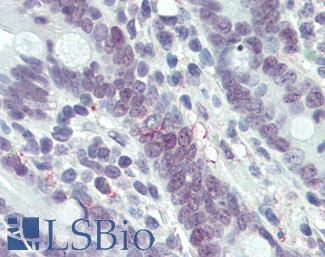

PDL1 (CD274)

Anti-B7-H1 / PD-L1 / CD274 antibody IHC staining of human testis. Immunohistochemistry of formalin-fixed, paraffin-embedded tissue after heat-induced antigen retrieval. Antibody LS-B10562 dilution 1:100.